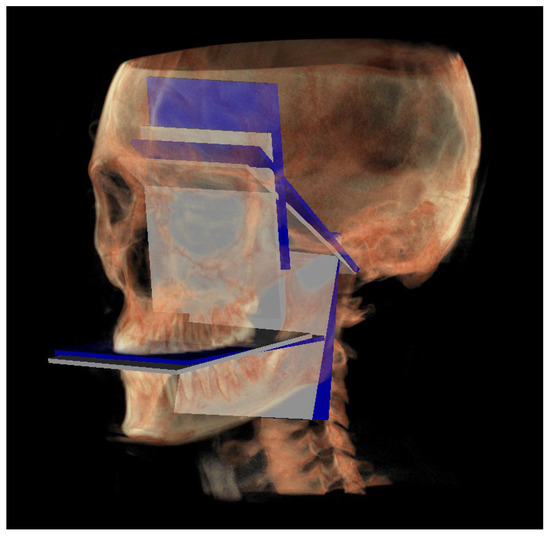

- PM (Figure 4) was identified by the points lMCF, rMCF and posterior nasal spine (PNS);

- The mandibular ramus plane (MR) (Figure 5) was identified by the following points: the middle points between the right and left condylion (mCo) and the right Gonion (rGo) and left Gonion (lGo). To adequately locate the mCo, it is advisable to draw a line on the frontal view from the right condylion to the left one to have a reference along which measure the mid-distance;

- The functional occlusal plane (FOP) (Figure 6) was identified by the posterior occlusal contact right side (rPoc), posterior occlusal contact left side (lPoc) and the middle point between the right and left anterior occlusal contact (mAoc). To adequately locate the mAoc, it is advisable to draw a line on the transversal view from the right mesial premolar contact to the left one to have a reference along which measure the distance.